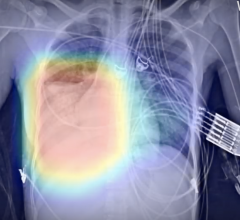

March 31, 2020 — Lung infections generated by the coronavirus can be detected in computed tomography (CT) images ...

March 31, 2020 — An artificial intelligence tool accurately predicted which patients newly infected with the COVID-19 ...

March 27, 2020 — Based on recent scientific research, diagnostic X-ray computed tomography (CT) is able to detect COVID ...